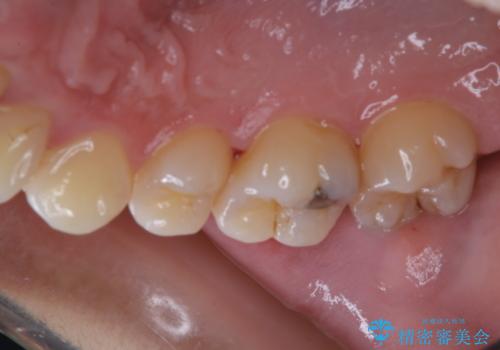

治療の前にPMTCできれいでツルツルな歯に

- 今後治療を進めていく予定で、まずはきれいにクリーニンングから行いたいとのことでした。PMTC60分コースを行いました。

PMTCを行う際には担当の歯科衛生士が、患者様1人1人の虫歯・歯周病などのリスク・ブラッシングスキルなどを確認します。

単なる磨き方の指導だけではなく、歯並びや歯肉の状態、ライフスタイルなどにより、患者様に適した歯ブラシや歯磨剤の選択をしたり、お口のお悩みについてのご相談も承っております。

定期的にPMTCでメンテナンスを行うことで、なにかあった時の早期発見につながります。

日々の磨き残しや唾液の成分などによりバイオフィルムや歯石はどうしても付着してしまいます。歯石や汚れを放置していると、そこで病原菌が繁殖す始めます。歯肉に炎症が生じると歯周病などの引き金となります。

そのため、2~3か月に1回は、歯科医院での専門的クリーニングをすることが大切です。